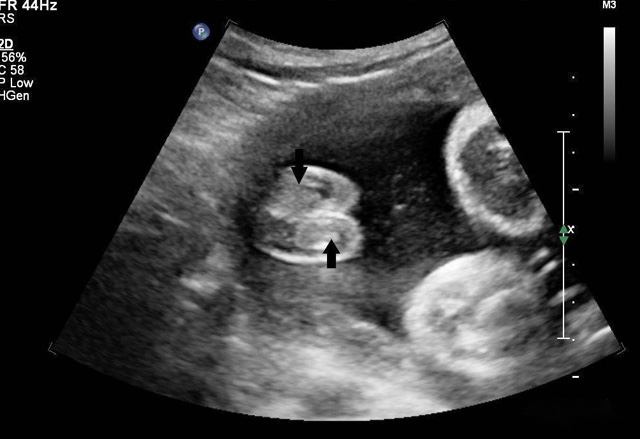

超聲波遇見散射體會發(fā)生散射強(qiáng)弱大小,形狀會周圍組織差別、聲阻抗很小散射很微弱,形狀及周圍組織的聲阻抗差別相關(guān)。血液內(nèi)盡管含有紅白細(xì)胞、血小板,普通超聲設(shè)備沒辦法顯示。人為加入不同介質(zhì)在血液中增強(qiáng)散射出現(xiàn)雨霧狀的回聲,這就是超聲造影的基本原理。組織對比超聲利用了這一原理。靜脈注射超聲造影劑隨著血液灌流而發(fā)展或增強(qiáng)器官和組織的成像,為臨床診斷提供成像數(shù)據(jù)基礎(chǔ)。